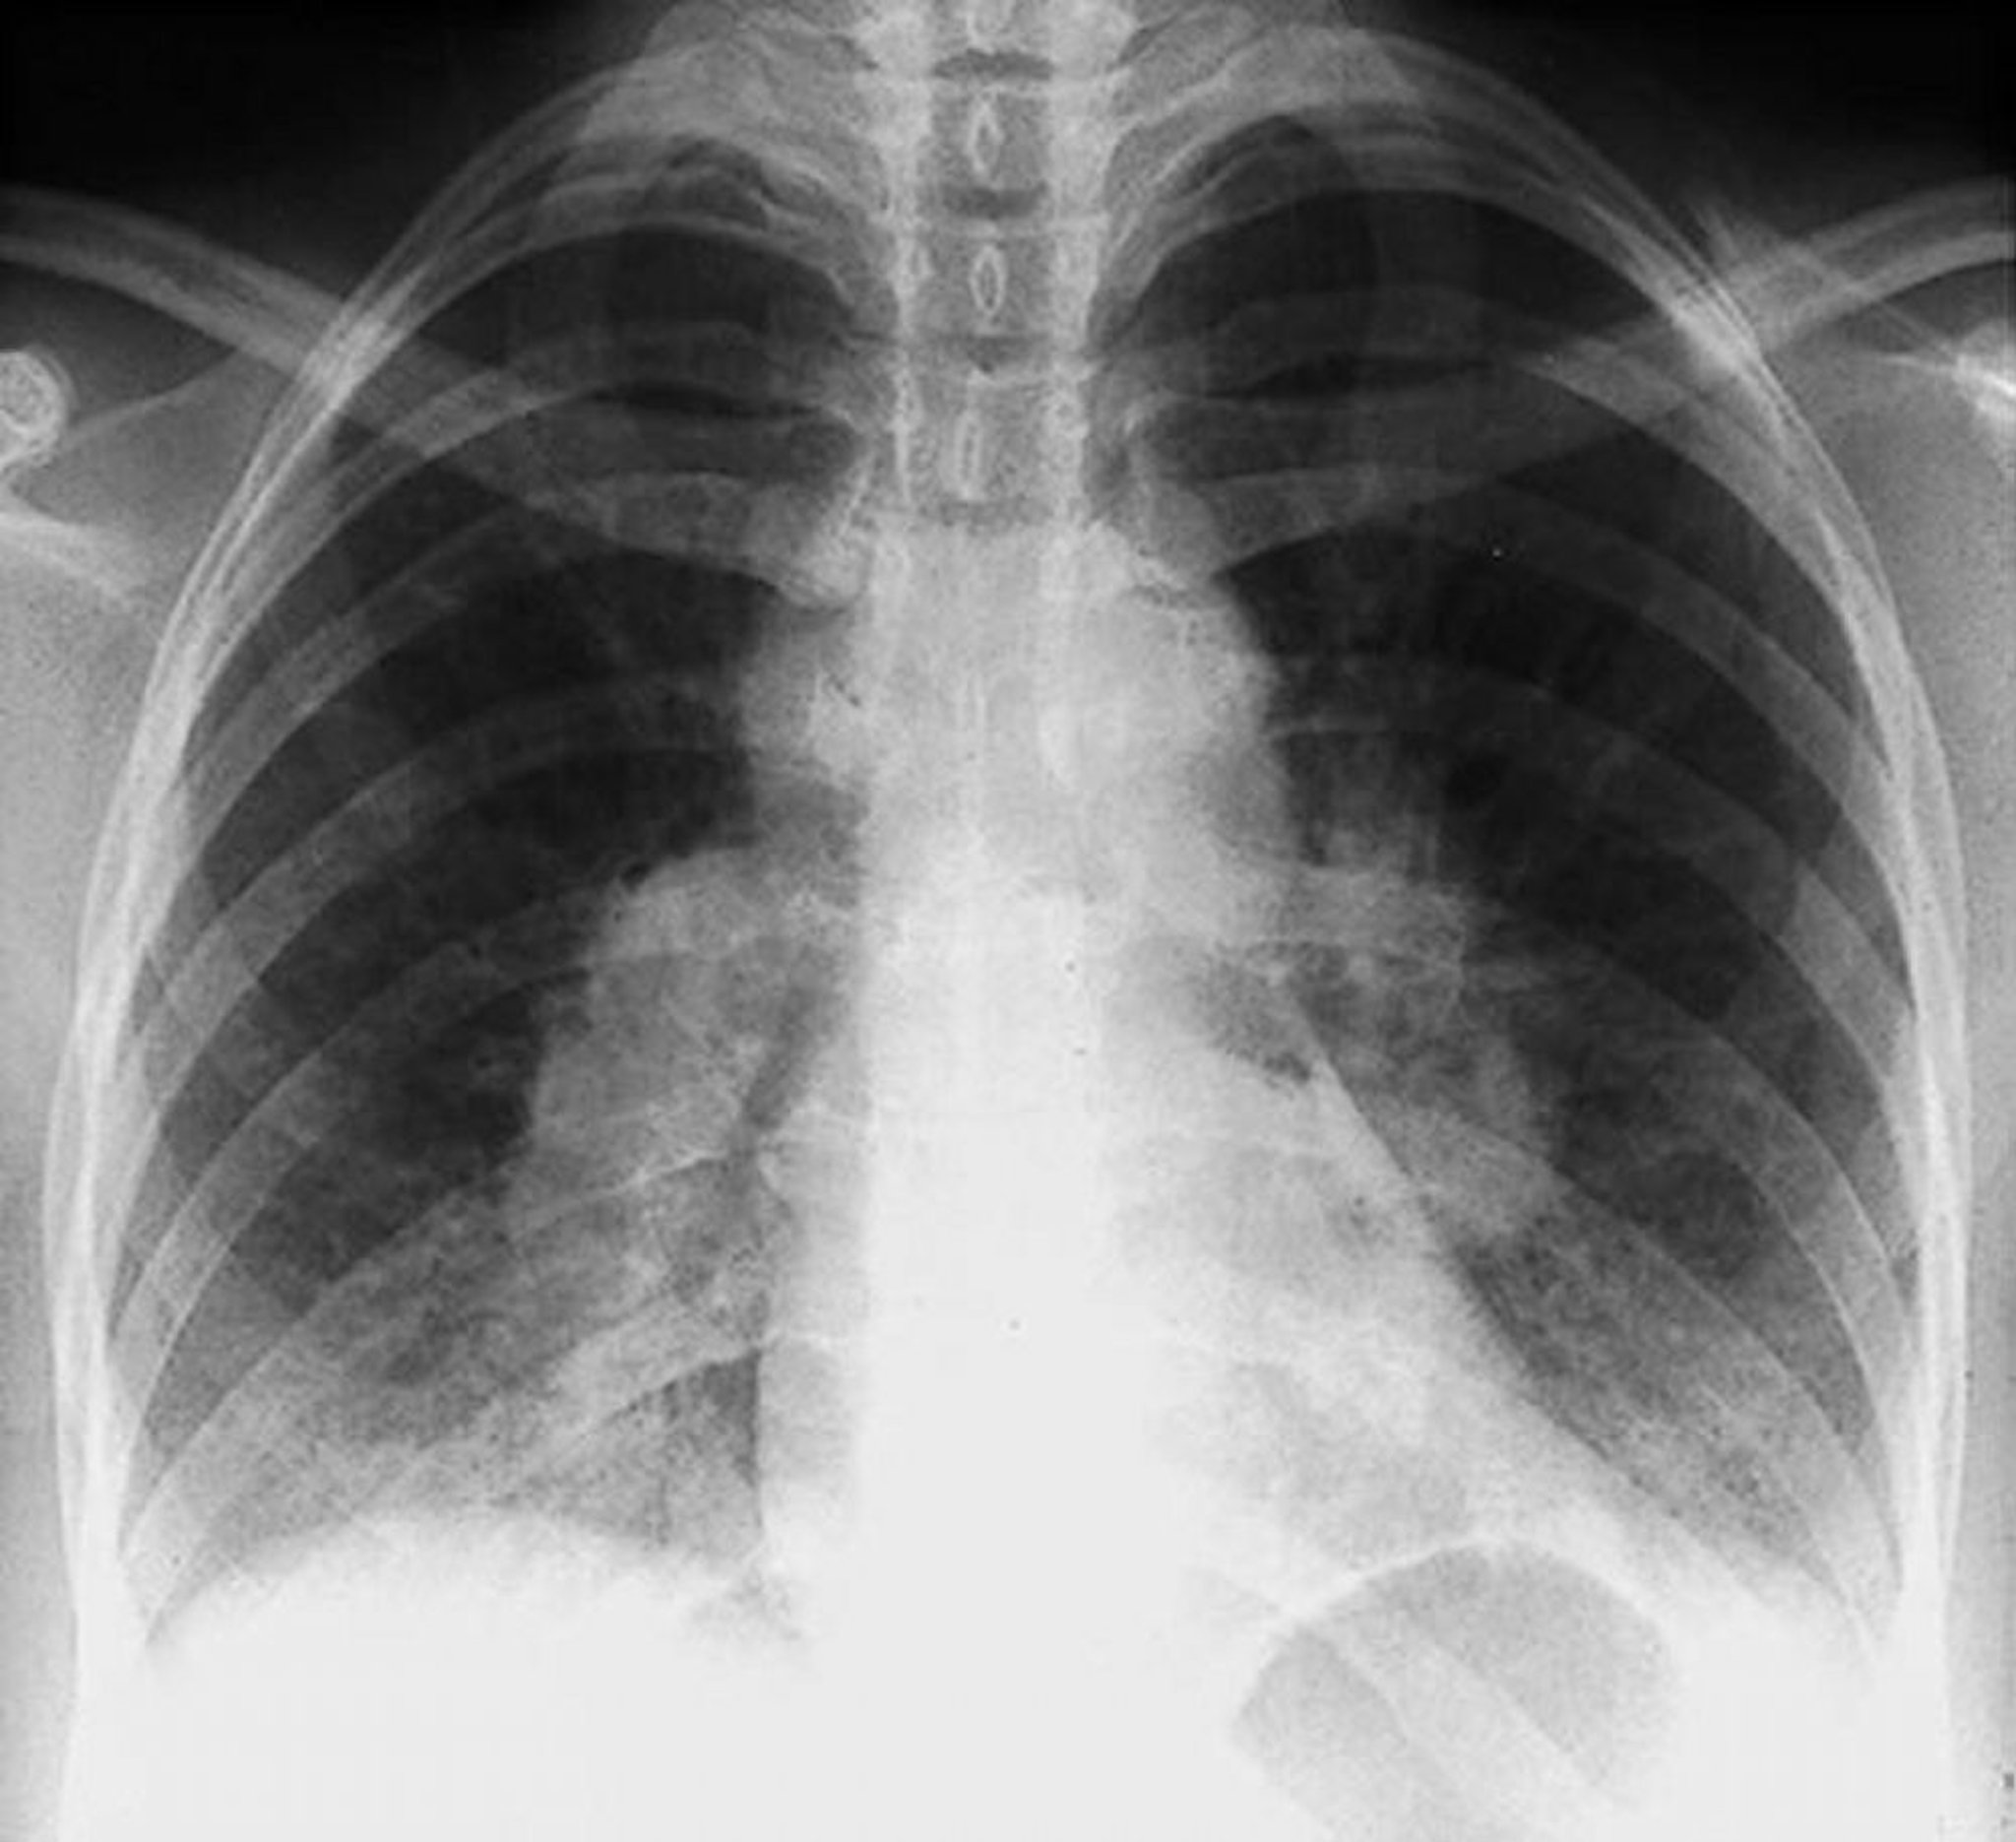

Sarcoidosis (estadio I)

Adenopatía hiliar bilateral en un estadio I de la sarcoidosis.

By permission of the publisher. De Tanoue L, Elias J. In Bone's Atlas of Pulmonary and Critical Care Medicine. Edited by J Crapo. Philadelphia, Current Medicine, 2005.